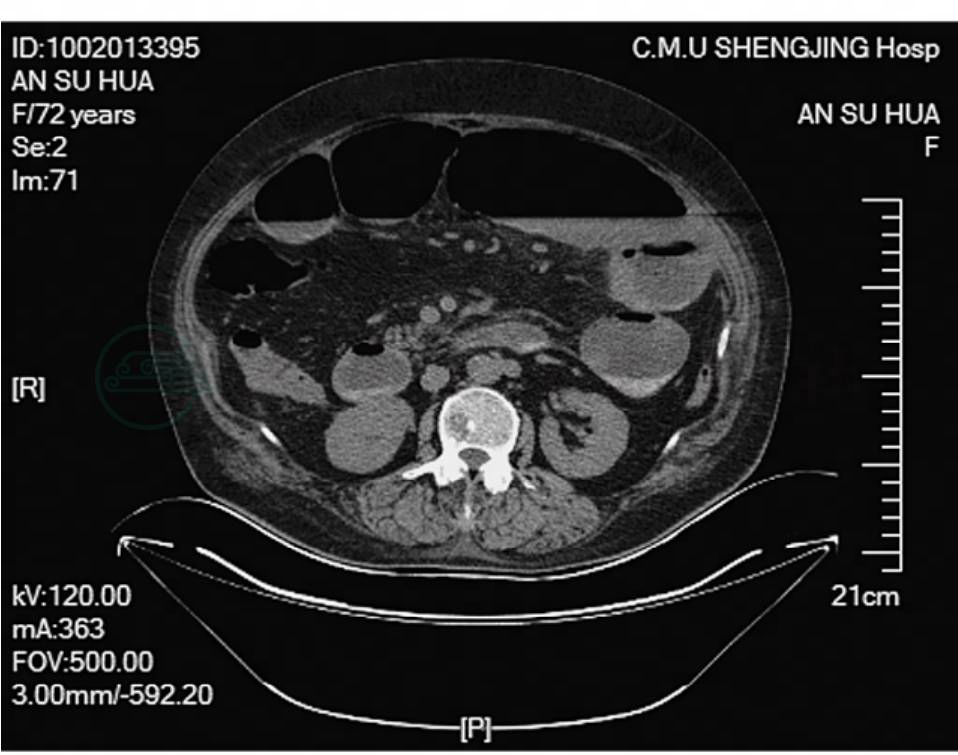

全腹CT平扫提示:肠梗阻;轻度脂肪肝;肝左外叶钙化或肝内胆管结石;子宫肌瘤伴钙化(图2,图3)。

图2 全腹CT平扫示肠梗阻(一)

图3 全腹CT平扫示肠梗阻(二)